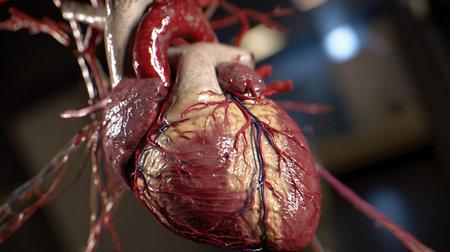

Живое сердце представляет собой мускулистый орган, который по размеру напоминает кулак человека. Оно имеет конусообразную форму и состоит из четырех камер: двух предсердий и двух желудочков. Поверхность сердца изолирована эпикардом, а внутреннюю часть выстилает эндокард, что обеспечивает гладкость и минимизацию трения во время сокращений.

Сердце активно функционирует, постоянно перекачивая кровь по всему организму, при этом его мышцы сокращаются ритмично и синхронно, обеспечивая бесперебойную работу. На его поверхности можно увидеть коронарные сосуды, которые снабжают кардиомиоциты кислородом и питательными веществами. Цвет живого сердца варьируется от ярко-красного до темно-красного, что обусловлено содержанием гемоглобина в крови.

Рис. 1. Строение стенок сердца.